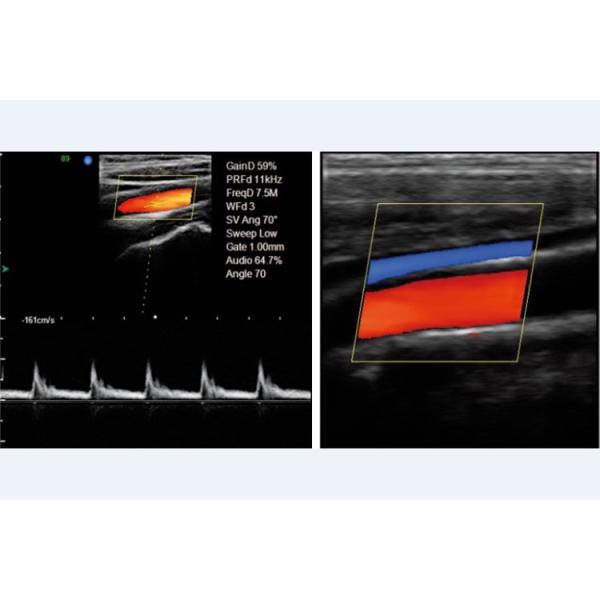

-Displaying mode

B, 2B, 4B, left&right, B|M, B|D, PW, M, B mode, part zoom, B|C|D, B|C|M, B|C,

duplex, PW, CFM, CPA

-Signal processing

Full-digital beam forming,

dynamic filter, orthogonal

demodulating,

space-time filter, dynamic

real-time receiving focusing, RDA, DRA, spectral processing, CFM processing

-Image processing

THI, speckle-reduction, color coder, frame averaging, micro- angle adjustment, wall filter, 256

grey scale, scanning angle/width control, composit processing of tissue and blood flow image